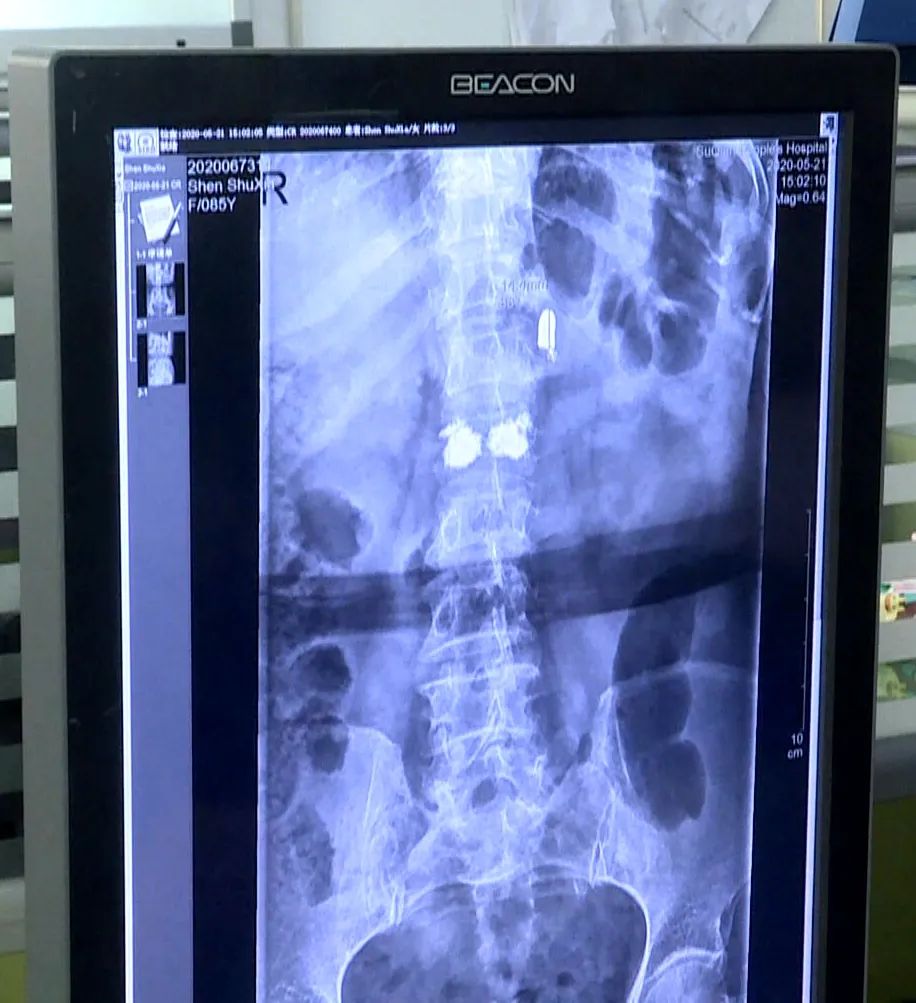

近日 , 江苏省宿迁市的85岁老人沈书侠遭遇车祸 , 腰椎骨折 。 医生手术透视过程中 , 在老人背部发现了一枚子弹 , 直径8毫米左右 , 长度15毫米左右 , 像是手枪的子弹 。

【子弹铁证!85岁老人体内发现80年前日军子弹!这是一个年代的悲剧】从沈书侠老人的X光片中能清楚地看到子弹头的影像